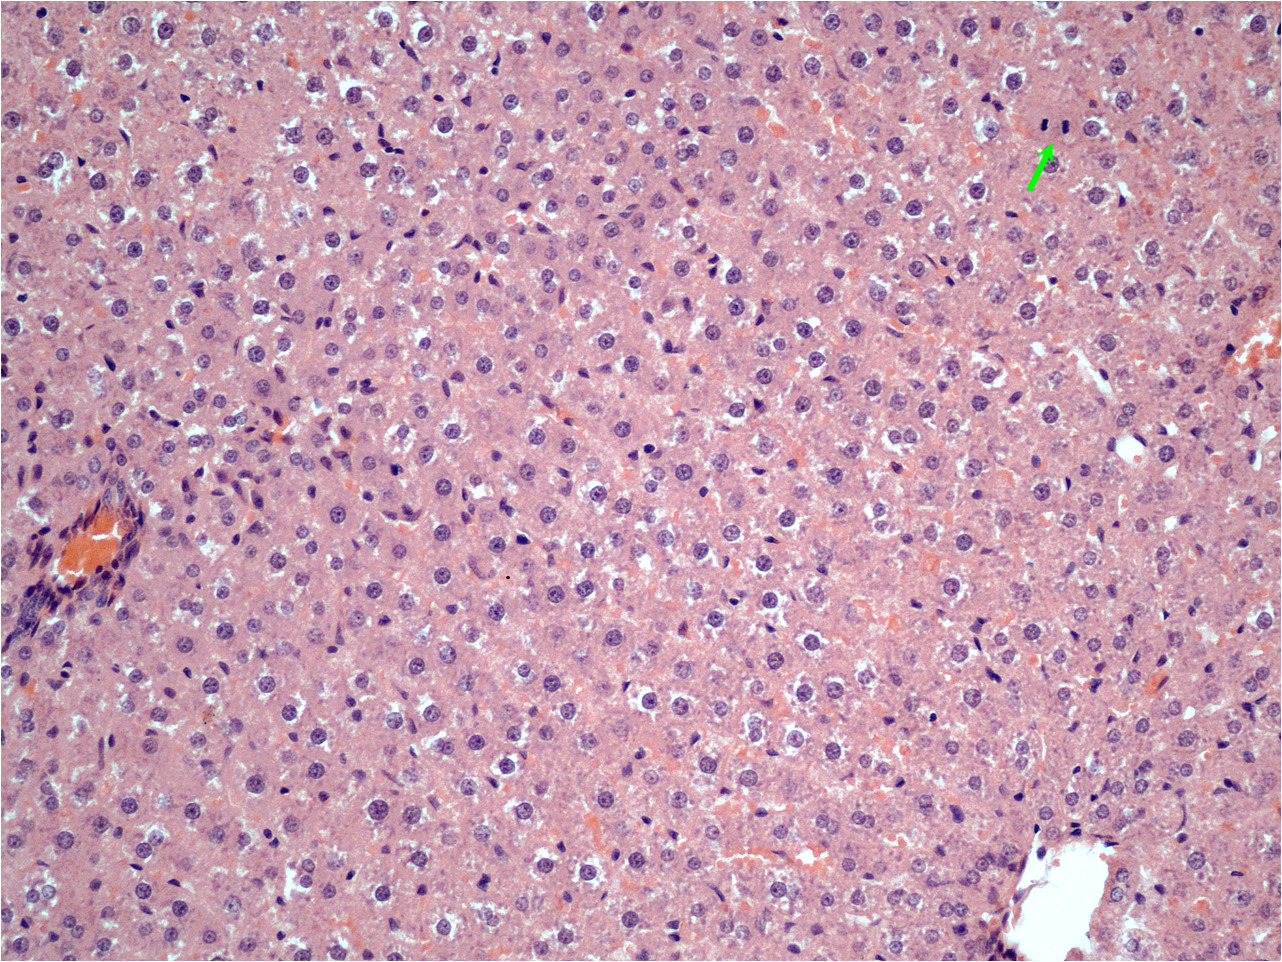

Результаты. Достоверного различия в массе прироста остатка печени и в биохимических показателях крови на сроке 48 часов после ОРП в обеих группах не обнаружено. Оценка митотического индекса гепатоцитов через 48 часов после ОРП выявила достоверное его увеличение в обеих группах по сравнению с исходным значением (до резекции печени), равным 0,14 ± 0,07‰. В первой группе животных величина МИ составила 12,70 ± 4,9‰, во второй группе – 17,43 ± 4,90‰, (p ≤ 0,05).

Заключение. Проведенные исследования регенерационной активности ТТС аминодигидрофталазиндиона натрия на экспериментальной модели ОРП у крыс показали выраженное стимулирующее воздействие данной лекарственной формы на митотическую активность клеток печени.